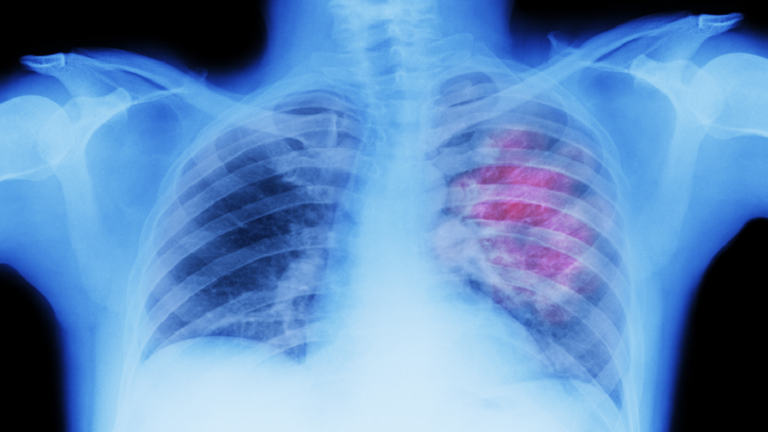

السوسنة - تشير التقارير الطبية إلى أن سرطان الرئة هو السبب الرئيسي الأول للوفيات الناتجة عن السرطان حول العالم.

ولا يتسبب سرطان الرئة عادة في ظهور أعراض في مراحله الأولى. ومع تقدم الحالة، يمكن أن تبدأ العلامات التحذيرية في الظهور.

أوضح طبيب الأورام السريري الدكتور نيل بايمان أن تكاثر الخلايا غير الطبيعية يمكن أن يشكل كتلة في الرئة، تعرف باسم الورم.

وأشار الدكتور بايمان إلى أن هناك نوعين رئيسيين من سرطان الرئة، الأول هو سرطان الرئة ذو الخلايا غير الصغيرة، وهو النوع الأكثر شيوعا ويمثل 90% من الحالات.

وتشمل سرطانات الرئة ذات الخلايا غير الصغيرة سرطان الخلايا الحرشفية والسرطان الغُدّي وسرطان الخلايا الكبيرة.

ويُعرف النوع الثاني بسرطان الرئة ذي الخلايا الصغيرة، والذي يمكن أن يمثل 10% أو أكثر من الحالات.

ويمكن أن تشمل مؤشرات الإصابة بسرطان الرئة "تعجر الأصابع" في اليد اليمنى، كما تشير مؤسسة Macmillan Cancer Support.

ويوصف تعجر الأصابع بـ"أن أطراف الأصابع تصبح أكثر انحناء أو أكبر حجماً". ويمكن أن تتضخم نهايات أطراف الأصابع في أي من اليدين، إلا أنها تحدث غالبا في اليد اليمنى.

ويُعتقد أن تعجّر الأصابع ناتج عن زيادة تدفق الدم إلى منطقة الأصابع، ما يؤدي إلى تراكم السوائل في الأنسجة الرخوة في أطراف الأصابع، ولكن ليس من الواضح تماما سبب حدوث ذلك.

وتميل التغييرات في الظفر إلى الحدوث على مراحل، حيث تصبح قاعدة الظفر ناعمة ويصبح الجلد بجوار فراش الظفر لامعا قبل أن تبدأ الأظافر في الانحناء أكثر من المعتاد.